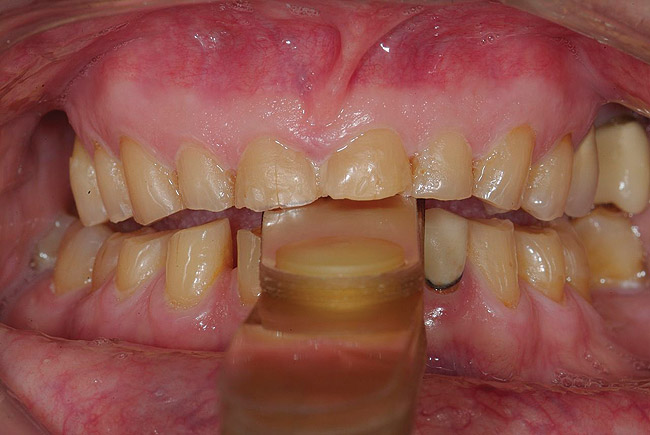

Figure 30  Final restorations.

Figure 30

Figure 31  Technical precision and artistic skill blend into a pleasing smile and a happy patient.

Figure 31